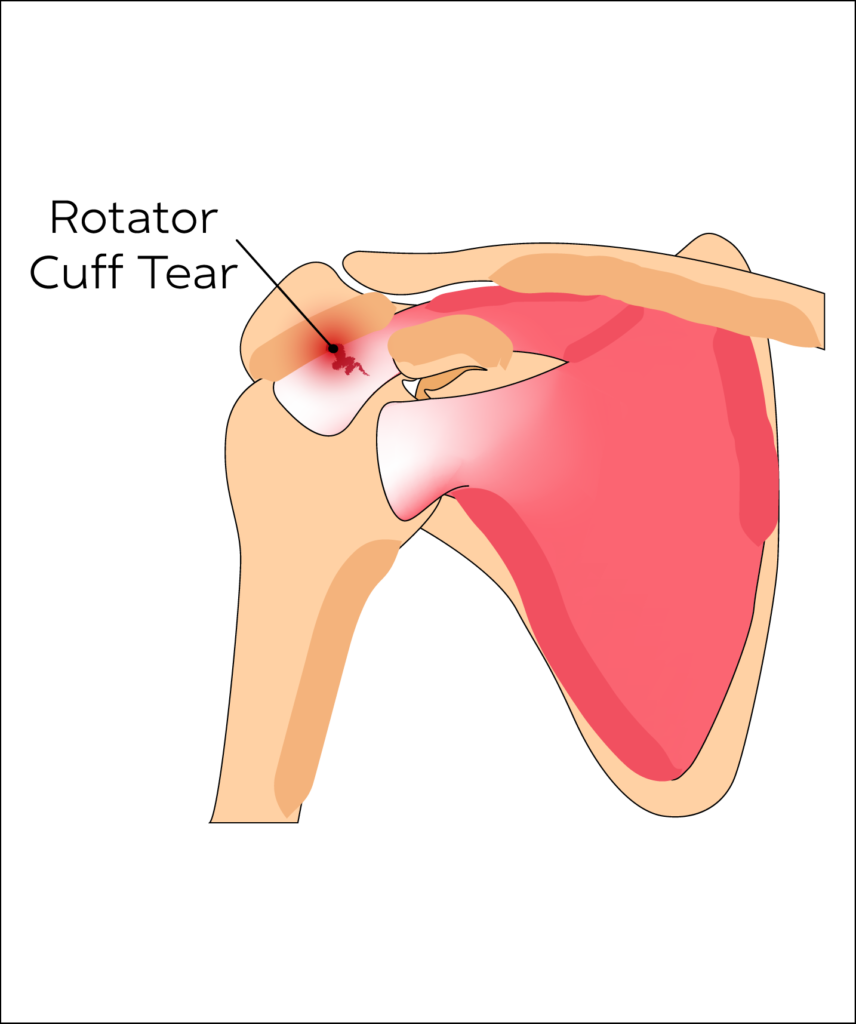

Rotator Cuff Tear

Rotator Cuff is a collective description for four muscles of the shoulder. A rotator cuff tear is a common injury in those who play sports or have repetitive work tasks. It can occur post injury or as a part of the ageing process.

Rotator Cuff Tears are common in adults.

The most common signs of a rotator cuff tear are pain while resting or at night especially whilst lying on the affected shoulder. Pain and crepitus (cracking)can occur on movement of the shoulder alongside restriction of movement. This in turn can lead to inflammation of bursa resulting in pain.

- Anti-inflammatory medication, ultrasound guided steroid injections (in selected cases of chronic tears) and physiotherapy are all common treatments for rotator cuff tears. There are also some regenerative medicine options.